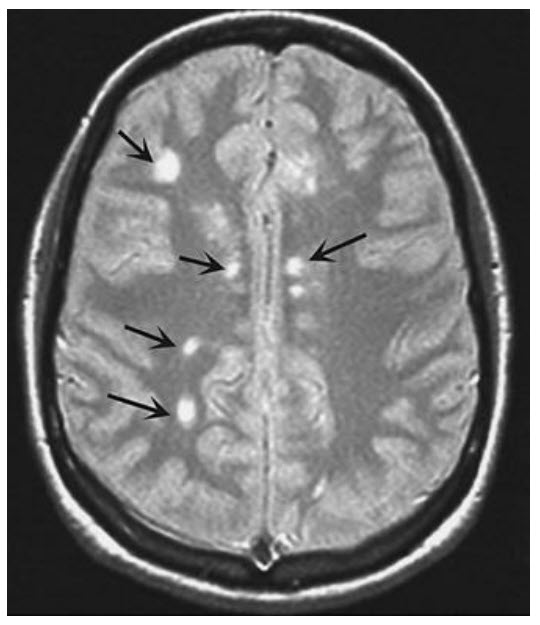

A 26-year-old woman presents for follow-up of her multiple sclerosis. She has had two separate episodes of optic neuritis and has noticed stutteringly progressive weakness in her lower extremities. She has a mild neurogenic bladder. Her symptoms have been stable over the past 4 months. MRI scanning reveals several plaques in the periventricular white matter (MR scan shown here) and several other plaques in the brainstem.

Interferon-beta is standard therapy used to prevent progressive disease in relapsing-remitting multiple sclerosis. Both interferon-beta 1b and several forms of interferon-beta 1a are available and are similarly effective. Glatiramer acetate (Copaxone) is also approved for MS. While patients who receive any one of these treatments have 30% fewer exacerbations and fewer new MRI lesions, the treatments do not cure the disease. Interferon-beta can cause side effects, particularly a flulike syndrome that usually resolves within several months. Acute exacerbations of MS are treated with high-dose methylprednisolone followed by tapering oral prednisone. This treatment improves symptoms during a relapse but does not appear to affect the long-term course of the disease. This patient, however, is not having an acute exacerbation of her disease. Steadily progressive MS, especially primary progressive disease, when the disease never remits but worsens inexorably, is a difficult management problem. Immunosuppressives such as cyclophosphamide and mitoxantrone are often tried. Such patients often progress to debility and mortality from urinary infection, aspiration pneumonia, or infected pressure ulcers. Simply providing this patient who has worsening disease with symptomatic treatment would be inappropriate.